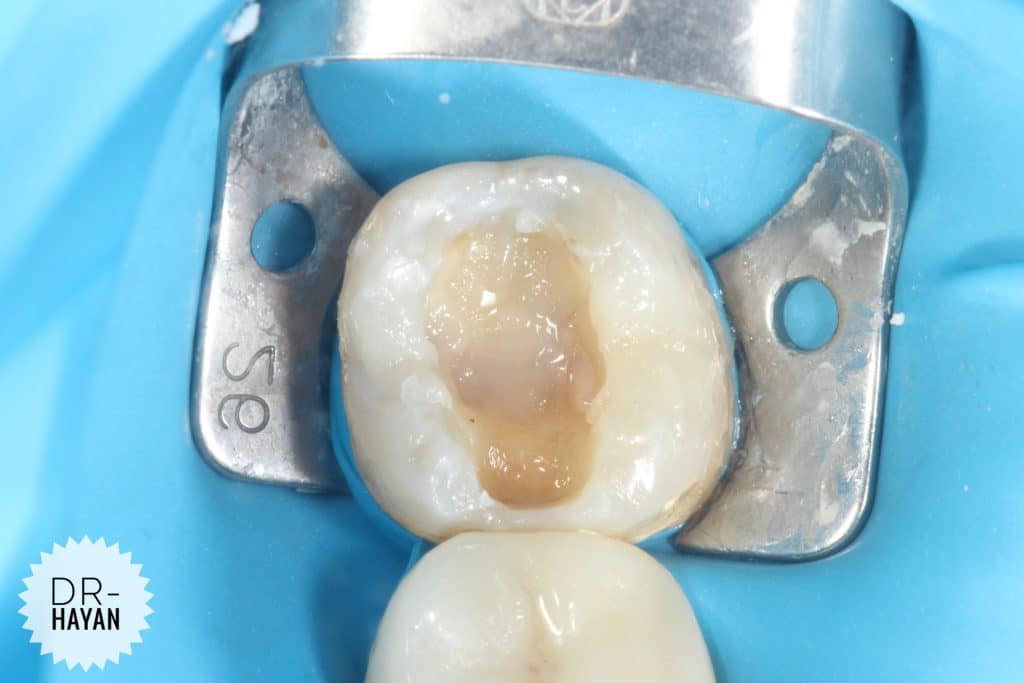

Initial view

lower 8 with Bad anatomy restoration & broken margin

With Sensitivity due to exposed dentin